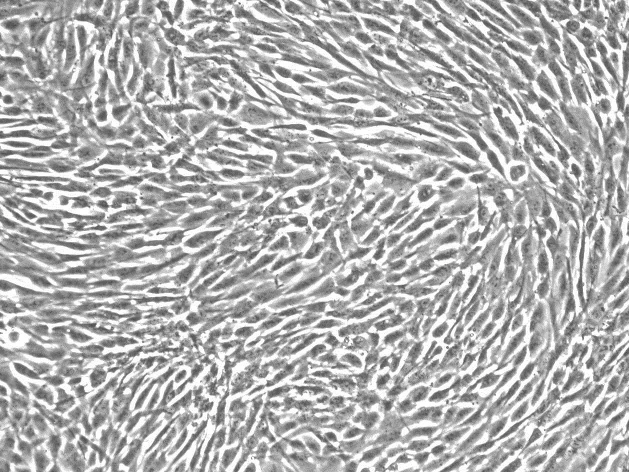

上皮细胞样

生长特性:贴壁细胞

细胞形态:上皮细胞样

背景描述:SW480人结直肠癌(通过STR鉴定)源自原位直肠腺癌,和SW620细胞源自同一病人一年后的淋巴结转移。CSAp和直肠抗体3阴性;角蛋白免疫过氧化物酶染色阳性。p53基因第273位密码子的G→A突变引起Arg→His替代,309位密码子的C→T突变导致Pro→Ser替代。细胞p53蛋白表达水平提高,癌基因c-myc、K-ras、H-ras、N-ras、myb、sis和fos的表达呈阳性,癌基因N-myc的表达未做检测。SW480 [SW-480]细胞不表达细胞溶解酶,一种与肿瘤入侵相关的金属蛋白酶。